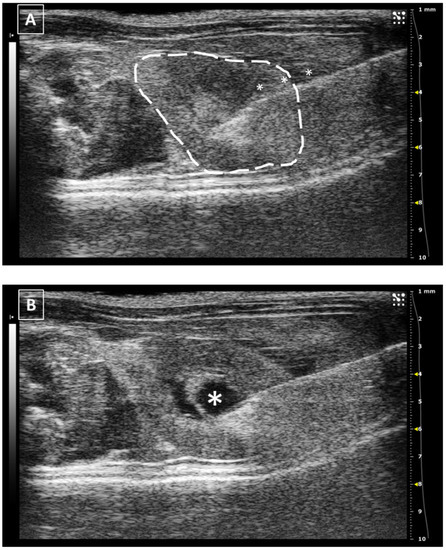

3.4. The Spleen

The spleen is a hypoechoic hematic organ, typically located on the left side of the abdomen, caudal to the stomach and lateral to the left kidney, but it can slide around the cranial part of the abdomen, especially during splenomegaly [25,26]. Due to this reason, the approach for its injection will depend on where it is located. In its usual place, a lateral approach is the best and easiest way of injecting. The animal should be placed in lateral recumbency, with the left side up. After shaving the hair, the scanning probe is placed over the last ribs and slowly displaced caudally. The spleen will appear on top of the screen, just under the skin. We will slightly balance the probe ventrally without losing sight of the structure and will insert the needle from the back of the animal. In a standardized view, the needle will arise from the right side of the screen and go medially. If the pressure from the ultrasound probe is enough, the spleen will be immobilized between it and the needle, and the injection will be performed easily. Similar to the liver, the maximum injected volume depends on the organ size but in previously published work we can find a range from 20 to 50 microliters [31]. After a few seconds, the needle can be removed and a last exam for the absence of bleeding should be performed. A representative image of the injection is shown in Figure 5.

Figure 5. Intrasplenic injection. Needle is marked with white asterisks and the spleen is surrounded by a dashed line. Stomach can be localized due to its typical acoustic shadow. Images obtained at 40 MHz frequency.